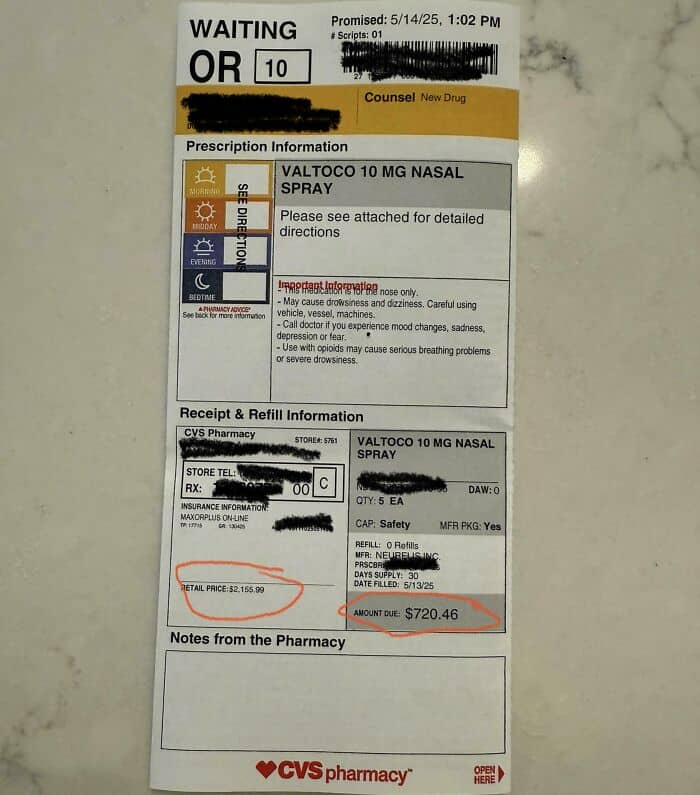

#56 My Son’s New Rescue Meds For Seizure Disorder, $2k Retail, $700 With Insurance

New rescue meds for 7-year-old with Lennox-Gastaut syndrome. Retail $2k. With insurance (BCBS), $700